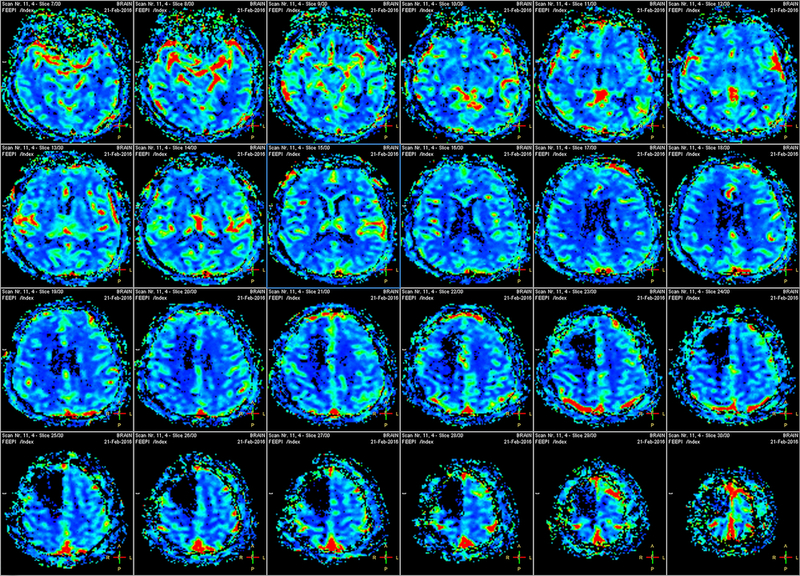

An fMRI machine tracks blood flow to activated brain areas. The assumption in concealed information detection is that the brain will show signs of recognition when presented with the concealed items while exerting extra effort to conceal signs of such recognition, and so the brain regions that do more work will get more blood. Such regions light up in scans, and they are primarily involved in directing attention and in decision making.